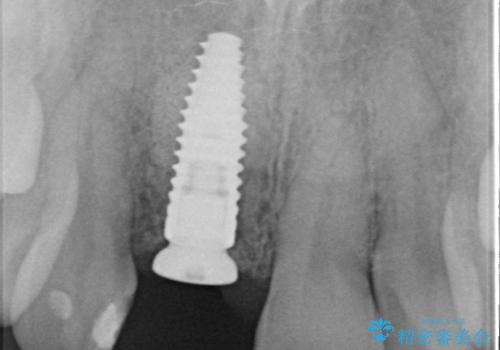

骨造成を伴う前歯のインプラント治療

審美的・機能的に良好な位置に埋入するには、骨量が十分ではなかったため骨の造成を併用したインプラント埋入外科手術を行います。

前歯のインプラントを審美的に仕上げるには、インプラント周囲に十分な骨の量と厚みのある歯肉、そして埋入位置の精密な位置付けが重要です。